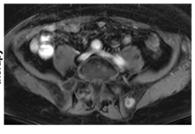

A) Coronal T2 IDEAL, B) axial diffusion tensor imaging (DTI), and C) coronal DTI fiber tracking sequences of the lumbosacral plexus and sciatic nerves demonstrates increased caliber and signal of the right sciatic nerve as it traverses the sciatic notch underneath the piriformis muscle.

D) Prone CT scan of the pelvis at the sciatic notch demonstrates a spinal needle placed at the sciatic nerve with injection of contrast and anesthetic: steroid mixture filling the perineural spaces of the sciatic nerve during a sciatic nerve block.